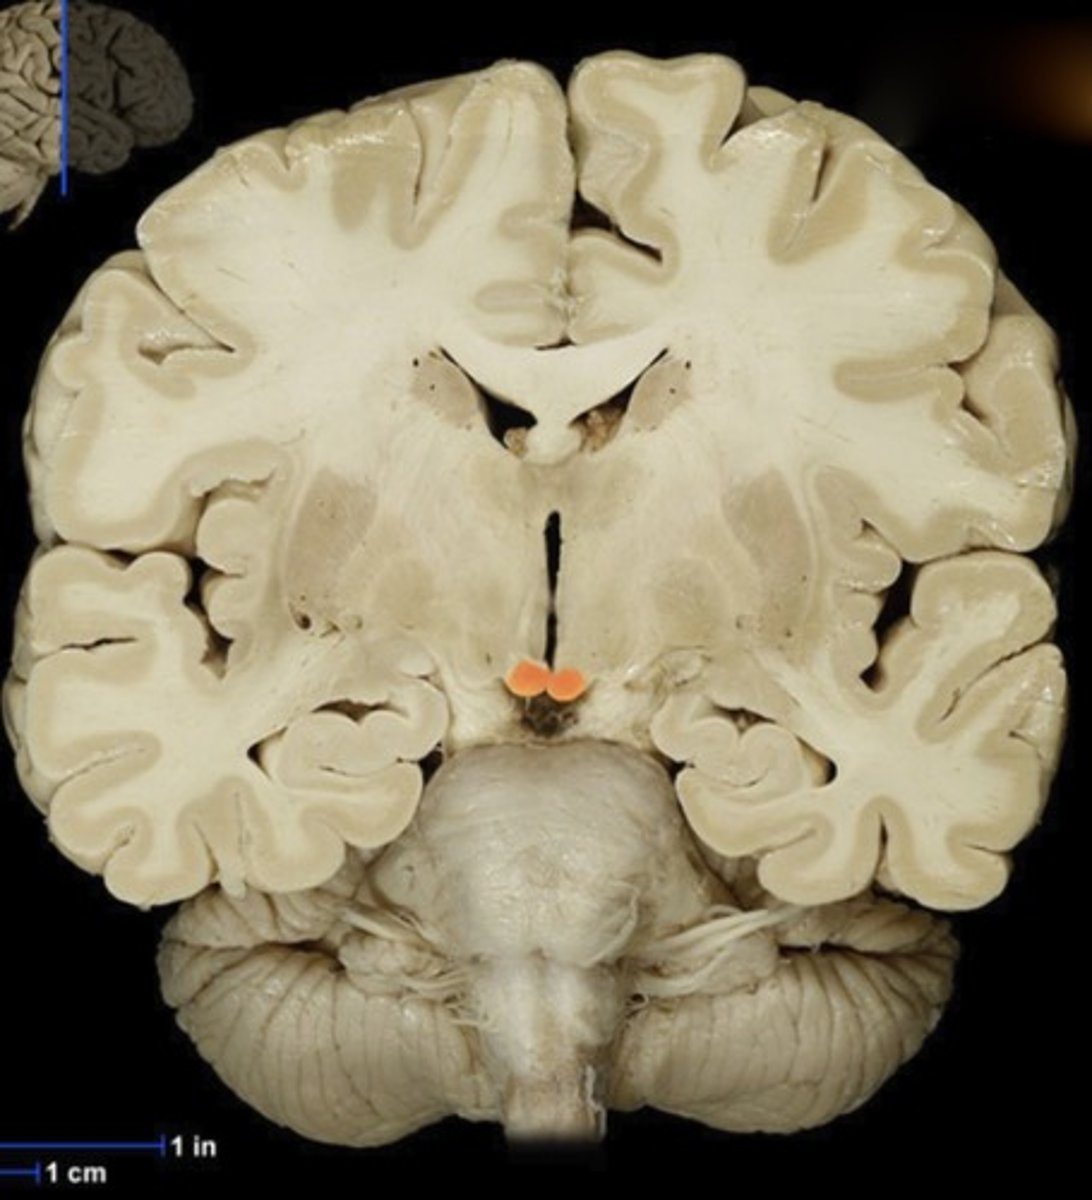

Caudate Nucleus

Name this structure

Gray matter (anterior view of coronal section)

Name this structure

White matter (anterior view of coronal section)

Name this structure

Corpus callosum

Name this structure

Fornix

Name this structure

Globus Pallidus

Name this structure

Hippocampus

Name this structure

Hypothalamus (anterior view of coronal section)

Name this structure

Lateral Ventricles

Name this structure

Mamillary body

Name this structure

Putamen

Name this structure

Thalamus (anterior view of coronal section)

Name this structure

Third Ventricle (anterior view of coronal section)

Name this structure